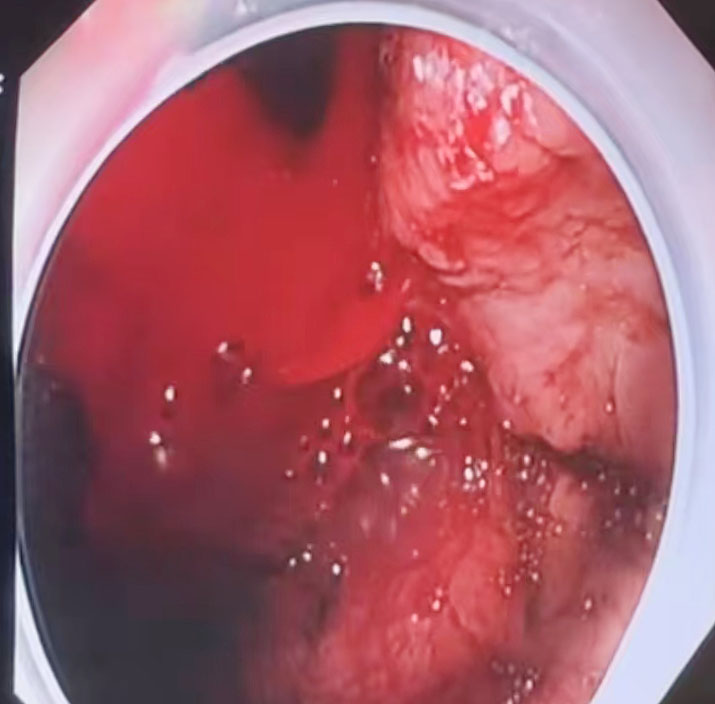

在气管插管麻醉下,医务处处长、内镜中心主任姚必瑜通过床旁内镜探查,“胃镜下可见,患者胃部有大量血液残留,胃底有一处静脉曲张破裂,正是出血根源。”姚必瑜立即使用硬化剂注射出血点,成功止血。